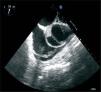

A 56-year-old man was admitted to our hospital for elective coronary angioplasty of a chronic total occlusion (CTO) of the right coronary artery (RCA). After insertion of a right femoral sheath, the RCA was engaged with a 6 French Amplatz AL-2 (Cordis, Miami, Fl, USA) guiding catheter. Recanalization was begun using a 0.014-inch Miracle 3 guidewire (Asahi Intecc, Japan). At this stage, an ostial dissection flap of the RCA with immediate retrograde extension to the ascending aorta was noticed (Figure 1). Stenting of the RCA ostium with a Xience Prime 3.0 × 15mm stent (Abbott Vascular, Santa Clara, California, USA) was performed, followed by a PTFE-covered 3.0 × 19mm Jostent graft (Jomed, Rangendingen, Germany), with apparent success. Transesophageal echocardiography showed a flap in the ascending aorta, extending up to the beginning of the aortic arch, with a partially thrombosed false lumen. No signs of pericardial effusion or aortic insufficiency were noted (Figure 2). A chest computed tomogram (CT) confirmed an ascending thoracic aorta dissection with a thrombosed false lumen 18mm in diameter, sparing the aortic arch (Figures 3 and 4A). The patient was admitted to the coronary care unit with mild chest pain but hemodynamically stable. He was managed conservatively. At the three-month follow-up visit, he was asymptomatic and the chest CT revealed complete resolution of the aorta parietal hematoma (Figure 4).